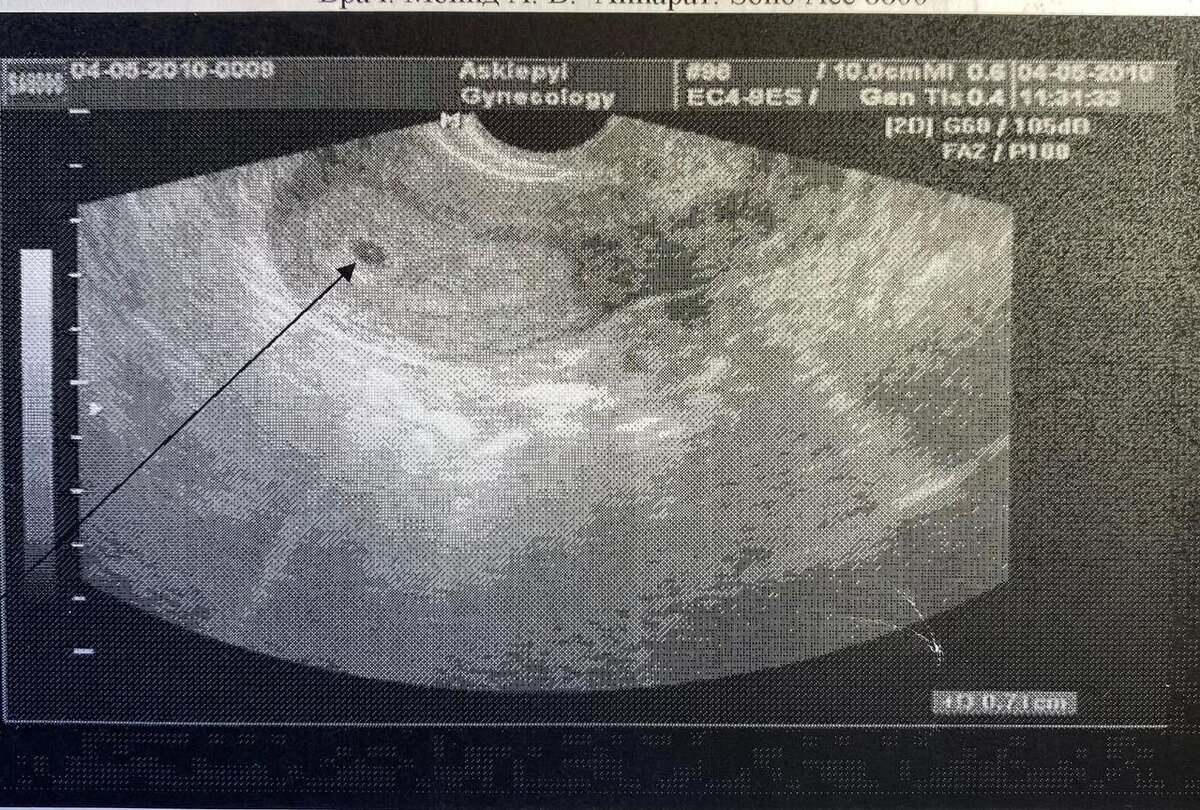

Я так сильно боялась его, что возможно ребенок передумал и решил уйти от меня самопроизвольный абортом. Я рыдала тогда как белуга. Я рыдала, что он ушел, ибо знал как я его боялась, и подумал, что я его не хотела. Но я его хотела. Несмотря на все эти перипетии страхов внутри меня — я его хотела. Я записалась на узи к лучшему генетику в городе и ждала этого дня — чтобы понимать, что там внутри меня все здорово или к чему готовиться.